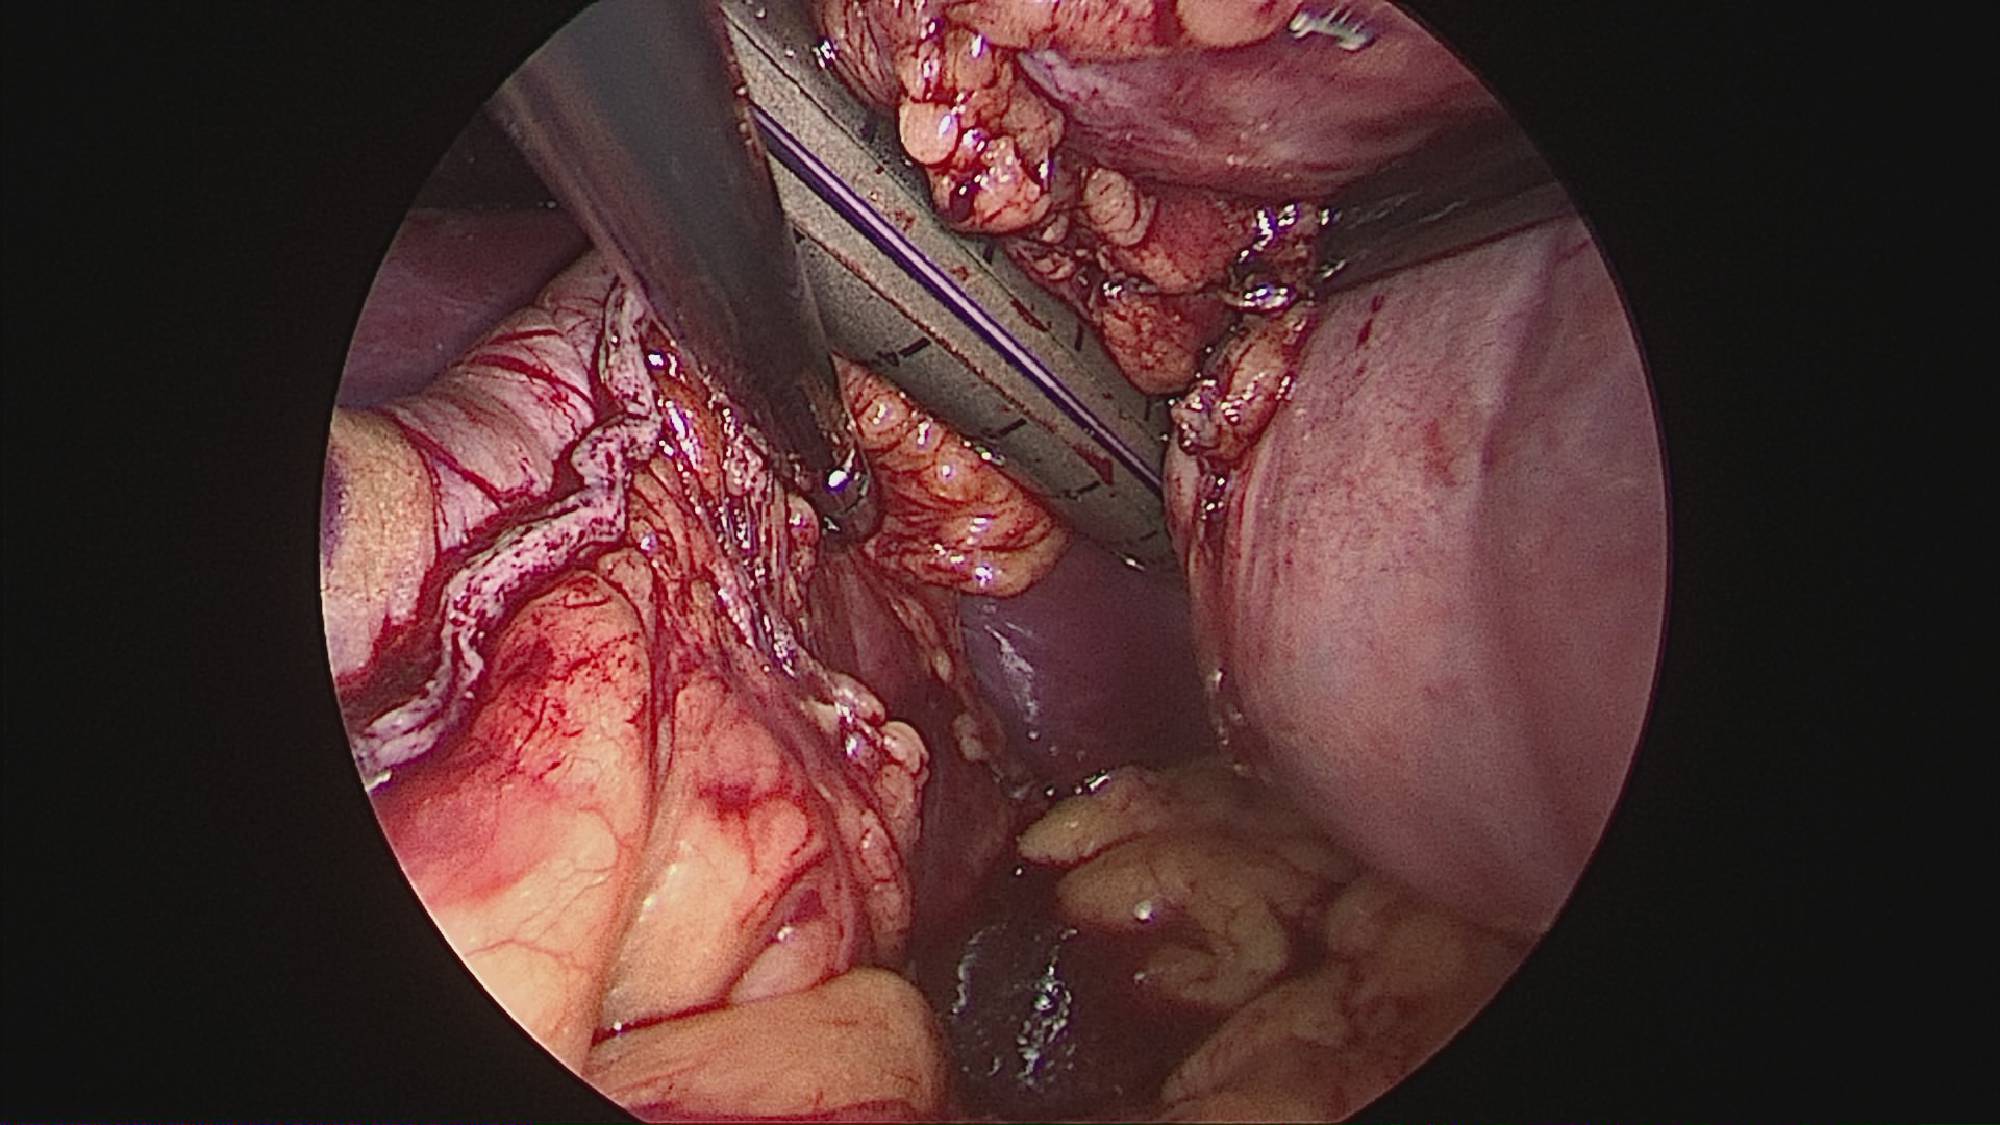

Operația ”de micșorare a stomacului” se realizează miniminvaziv (laparoscopic) și constă în îndepărtarea marii curburi gastrice cu păstrarea antrului gastric și a micii curburi sub forma unui tub calibrat pe o sondă.